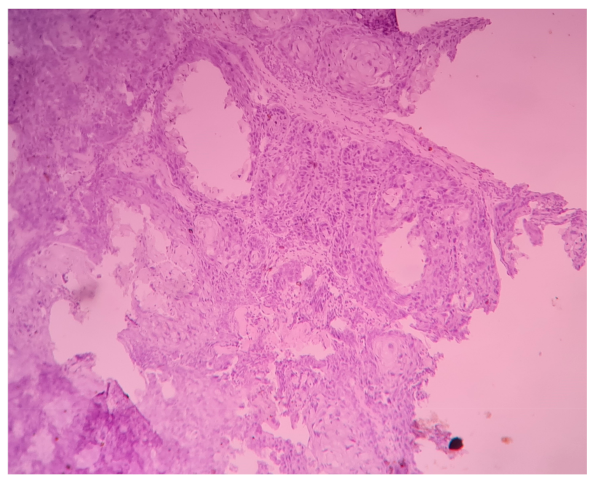

| Histopathology Grading Well Moderate Poor | 33 16 1 | 66.0 32.0 2.0 |